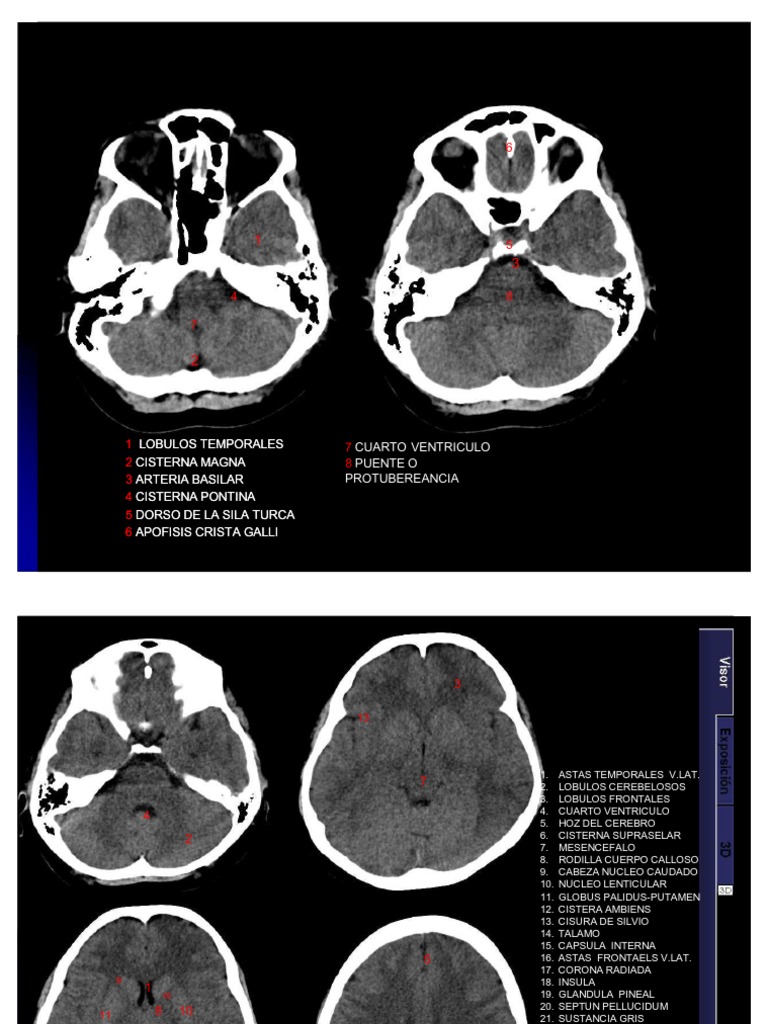

Lectura Sistematica Del Tc De Craneo